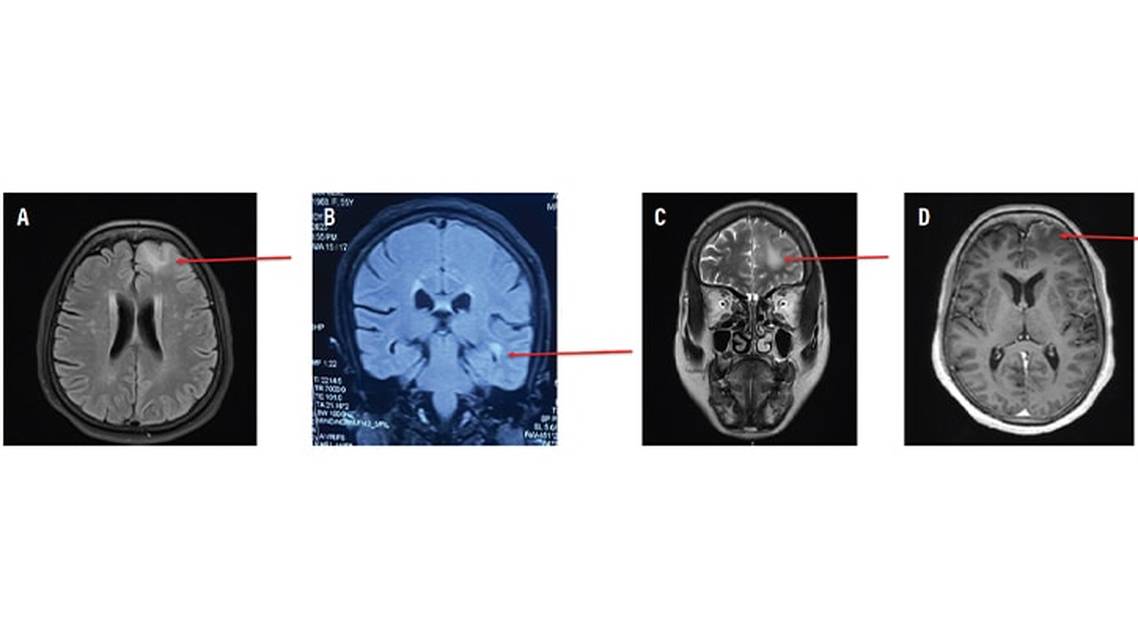

MRI brain scan (Figure 1) showed left focal frontal T2 hyperintensity with focal leptomeningeal enhancement. A T2 hyperintense lesion was present at the junction of the left insular region and the left medial temporal lobe. The latter lesion did not demonstrate any contrast enhancement. Figure 2 presents a timeline of the illness course.

Focal cortical T2 hyperintensities in individuals with LGI1 antibody encephalitis have not been reported previously in the literature. HB had left focal frontal cortical T2 hyperintensities with focal leptomeningeal enhancement (Figure 1). The differential diagnosis for focal cortical encephalitis includes viral encephalitis, MOG antibody–associated disease (MOGAD),7 Rasmussen encephalitis,8 and postictal MRI change. In HB, viral etiology was ruled out by CSF analysis, the age at presentation made Rasmussen encephalitis highly unlikely, and the persistence of signal changes on serial MRI made postictal MRI abnormality unlikely, because these changes usually resolve on serial imaging.9 Because co-occurrence of LGI1 and MOG antibodies has been reported, and the presence of fluid-attenuated inversion recovery–hyperintense lesions in anti–MOG-associated encephalitis with seizures (FLAMES) is a known presentation of MOGAD, we performed serum MOG antibody testing for HB; results were negative, ruling out MOGAD.7